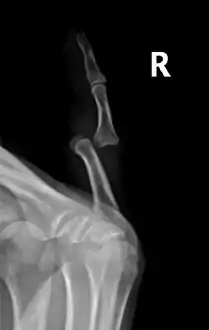

A traumatic dislocation of the tibiotarsal joint of the ankle with distal fibular fracture. Open arrow marks the tibia and the closed arrow marks the talus.